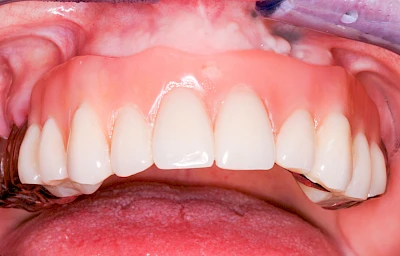

Ist zunächst nur das Zahnfleisch von der Entzündung betroffen, spricht man von Gingivitis. Später, wenn auch der Knochen um die Zähne herum entzündet ist, spricht man von einer Parodontitis. Bei der Parodontitis wird der Knochen nach und nach abgebaut und das Zahnfleisch zieht sich zurück. Die Zahnhälse und Zahnwurzeloberflächen liegen mehr und mehr frei. Die Zähne werden zunehmend lockerer und fallen schließlich aus.

Gingivitis & Parodontitis: Stadien